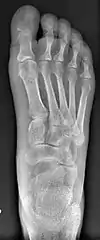

Bunion (hallux valgus) deformity is actually part of a complex of anatomical derangements of protruding mass (bunion), buckling of big toe (hallux valgus) and the bone behind it (metatarsus primus varus), displaced sesamoid bones (detrimental to the important walking function of big toe), collapsed metatarsal arch and several other secondary changes that are the domino effects of metatarsal primus varus. Thus, metatarsus primus varus correction has become the primary objective of all bunion surgeries.

Primus varus deformity

Primus varus deformity is the leaning of the first metatarsal bone away from the second metatarsal and towards the opposite foot (Fig. 1). As it leans over, its head sticks out to form the bunion bump and it also widens the forefoot to cause shoes feeling too tight. Thus when bunion pain becomes unmanageable, surgical correction is to narrow the forefoot by repositioning of the first metatarsal head back to its normal position. This can be done by osteotomy (bone-breaking), soft tissue (non-osteotomy) or fusion techniques.

Syndesmosis procedure addresses specifically the two fundamental problems of metatarsus primus varus deformity that gives rise to the bunion deformity. They are leaning and instability of the first metatarsal bone . Syndesmosis procedure uprights the leaning first metatarsal bone with strong binding sutures between it and the second metatarsal bone (Fig. 2) and then also stabilizes it uniquely by creating a fibrous connecting bridge between these two bones (Fig. 3, 4). First metatarsal bone can be readily realigned because by definition of the metatarsus primus varus deformity its first metatarsal is abnormally loose and mobile.